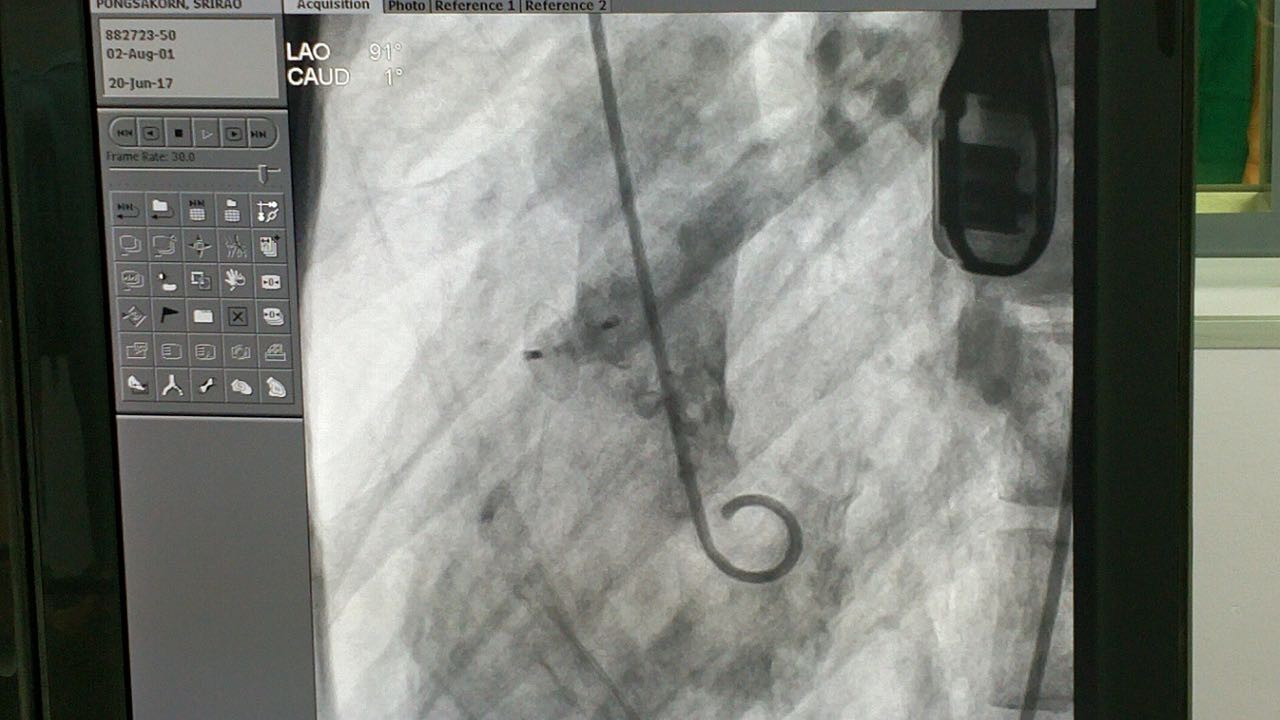

第四例手术患者经诊断为膜周部室距离缺损并伴有室缺瘤。术中丈量患者瘤体直径为12.5mm,左室入口为9.92mm,右室出口为3.27mm,且其室距离缺损地位较为特殊,位于自动脉瓣正后方并非?拷獍。病人同时拥有三尖瓣反流的症状。本例手术的重要术者Dr.Pimpak Prachasilchai选用俄罗斯贵宾会集团科技公司型号为LT-MFO-8-6的KONAR-MF?多职能封堵器,通过自动脉蹊径开释成功。病人缺损部位封堵齐全,无残存分流,三尖瓣未受滋扰。

(术中造影)